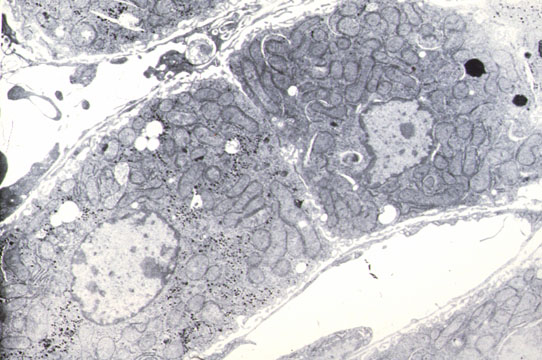

Fig 9 - BILE DUCTULES, CHOLANGIOLES, CANALS OF HERING

In the periportal region the biliary tree takes origin. The bile canaliculus lined by hepatocytes meets the ductule, first lined by hepatocytes and ductal epithelium, then lined only by ductal cells. They penetrate the portal space and connect with the interlobular bile duct. Bile ductules have a basal lamina. The ductal epithelium is cuboidal with light stained cytoplasm, dark nuclei and few cytoplasmic organelles.